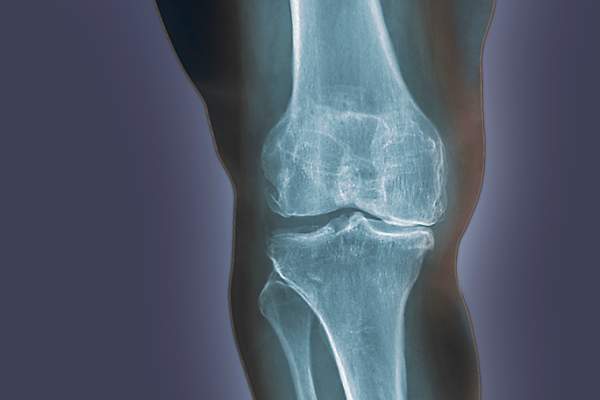

当作为缓冲的骨头之间的软骨开始破裂,骨头开始与骨头摩擦,它会导致骨关节炎,或关节疼痛的肿胀。OA会导致早上第一件事就是僵硬,在某些活动中或活动后会引起疼痛和疼痛。根据关节炎基金会,OA是最常见的关节炎类型。通常当你听到某人谈论普通的旧“关节炎”,OA是他们的意思。大多数患有OA的人在50多岁的时候会患上这种疾病,但也有一些人会因为受伤或肥胖而患上这种疾病。